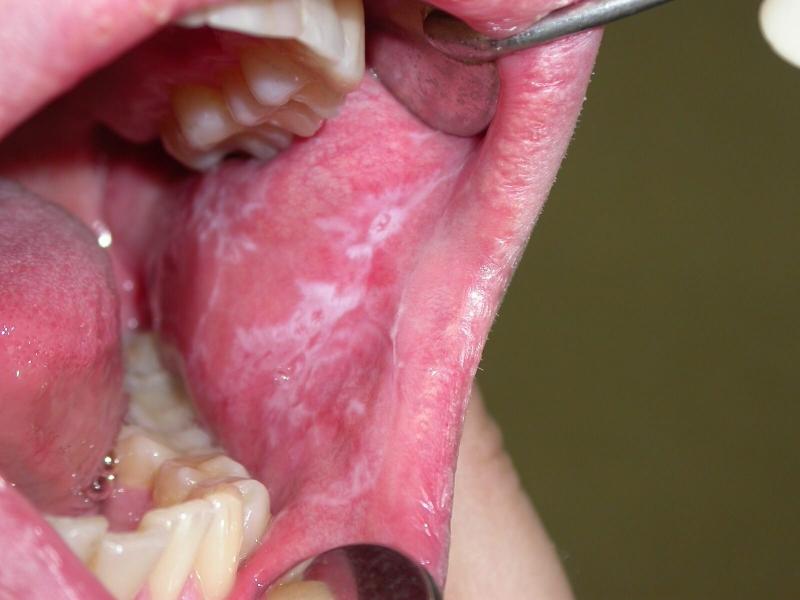

Стоматит может легко распространиться с поражённой щеки на язык, мягкое нёбо, губы и миндалины.

В зависимости от типа стоматита, течение болезни может варьироваться. Тем не менее, все формы стоматита имеют общие симптомы, которые являются достаточным основанием для срочного обращения к стоматологу:

- Щека опухла, слизистая оболочка покраснела и болит;

- На поражённой области появились гнойные язвы;

- Наблюдается значительное увеличение слюноотделения, дёсны кровоточат, а изо рта исходит неприятный запах;